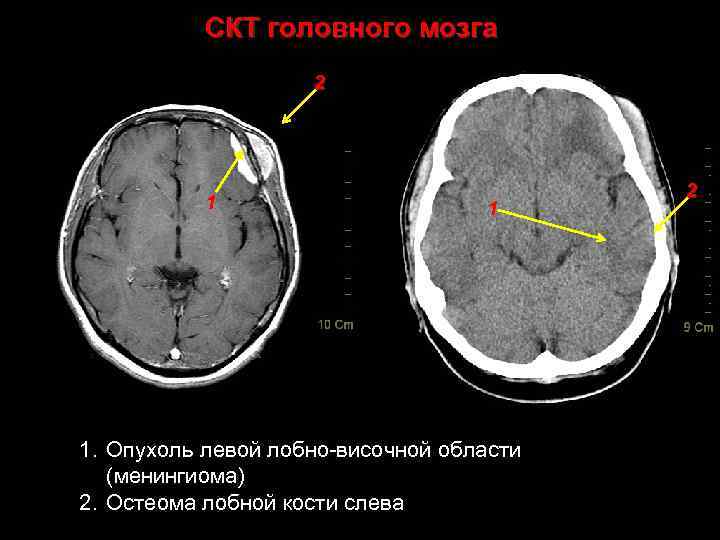

СКТ головного мозга 2 1 1. Опухоль левой лобно-височной области (менингиома) 2. Остеома лобной кости слева. 49